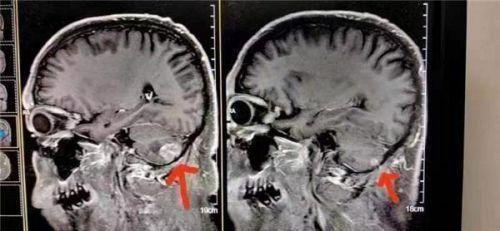

病例22:癌症小细胞脑转移

患者在北京301医院接受检查和治疗,结果显示左脑肿瘤大于右脑肿瘤。陈海林采用纯中药临床治疗,经过三个月的治疗,于2023年6月28日进行了脑磁共振平扫,共10个对比:1。与2023年3月9日的MR片相比,右小脑转移瘤复查,病变基本消失。这一结果甚至被301医院称为奇迹。

Case 22: Small cell lung cancer with brain metastasis

The patient underwent examination and treatment at Beijing 301 Hospital, and the results showed that the left brain tumor was larger than the right brain tumor. Chen Hailin adopted clinical treatment with pure Chinese medicine, and after three months of treatment, on June 28, 2023, the brain magnetic resonance plain scan with ten contrasts: 1. Compared with the MR film on March 9, 2023, the right cerebellar metastatic tumor reexamined and the lesion basically disappeared. This result is even claimed to be a miracle by Hospital 301.